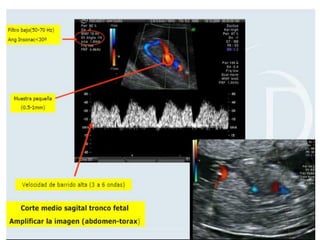

VALORACIÓN DV

• Semanas 11+0-13+6 y la LCC entre 45-84 mm. El feto no

debe moverse.

• El tamaño de la imagen debe ser tal que el tórax y abdomen

fetal ocupen toda la pantalla. Se debe obtener un corte

sagital medio del tronco fetal.

• Se debe usar el Doppler color para demostrar la vena

umbilical, el ductus venoso y el corazón fetal. La ventana

del Doppler pulsado debe ser pequeña (0,5-1,0 mm) y debe

situarse en la zona de aliasing normalmente en amarillo

• El ángulo de insonación debe ser menor de 30 grados.

• El filtro debe ser de baja frecuencia (50-70 Hz), para

permitir la visualización de la onda completa.

• La velocidad de barrido debe ser alta (2-3 cm/s), para

obtener una forma más ancha y poder evaluar mejor la onda

A.

VALORACIÓN DV • Semanas11+0-13+6 y la LCC entre 45-84 mm. El feto no debe moverse. • El tamaño de la imagen debe ser tal que el tórax y abdomen fetal ocupen toda la pantalla. Se debe obtener un corte sagital medio del tronco fetal. • Se debe usar el Doppler color para demostrar la vena umbilical, el ductus venoso y el corazón fetal. La ventana del Doppler pulsado debe ser pequeña (0,5-1,0 mm) y debe situarse en la zona de aliasing normalmente en amarillo

VALORACIÓN DV • Elángulo de insonación debe ser menor de 30 grados. • El filtro debe ser de baja frecuencia (50-70 Hz), para permitir la visualización de la onda completa. • La velocidad de barrido debe ser alta (2-3 cm/s), para obtener una forma más ancha y poder evaluar mejor la onda A.